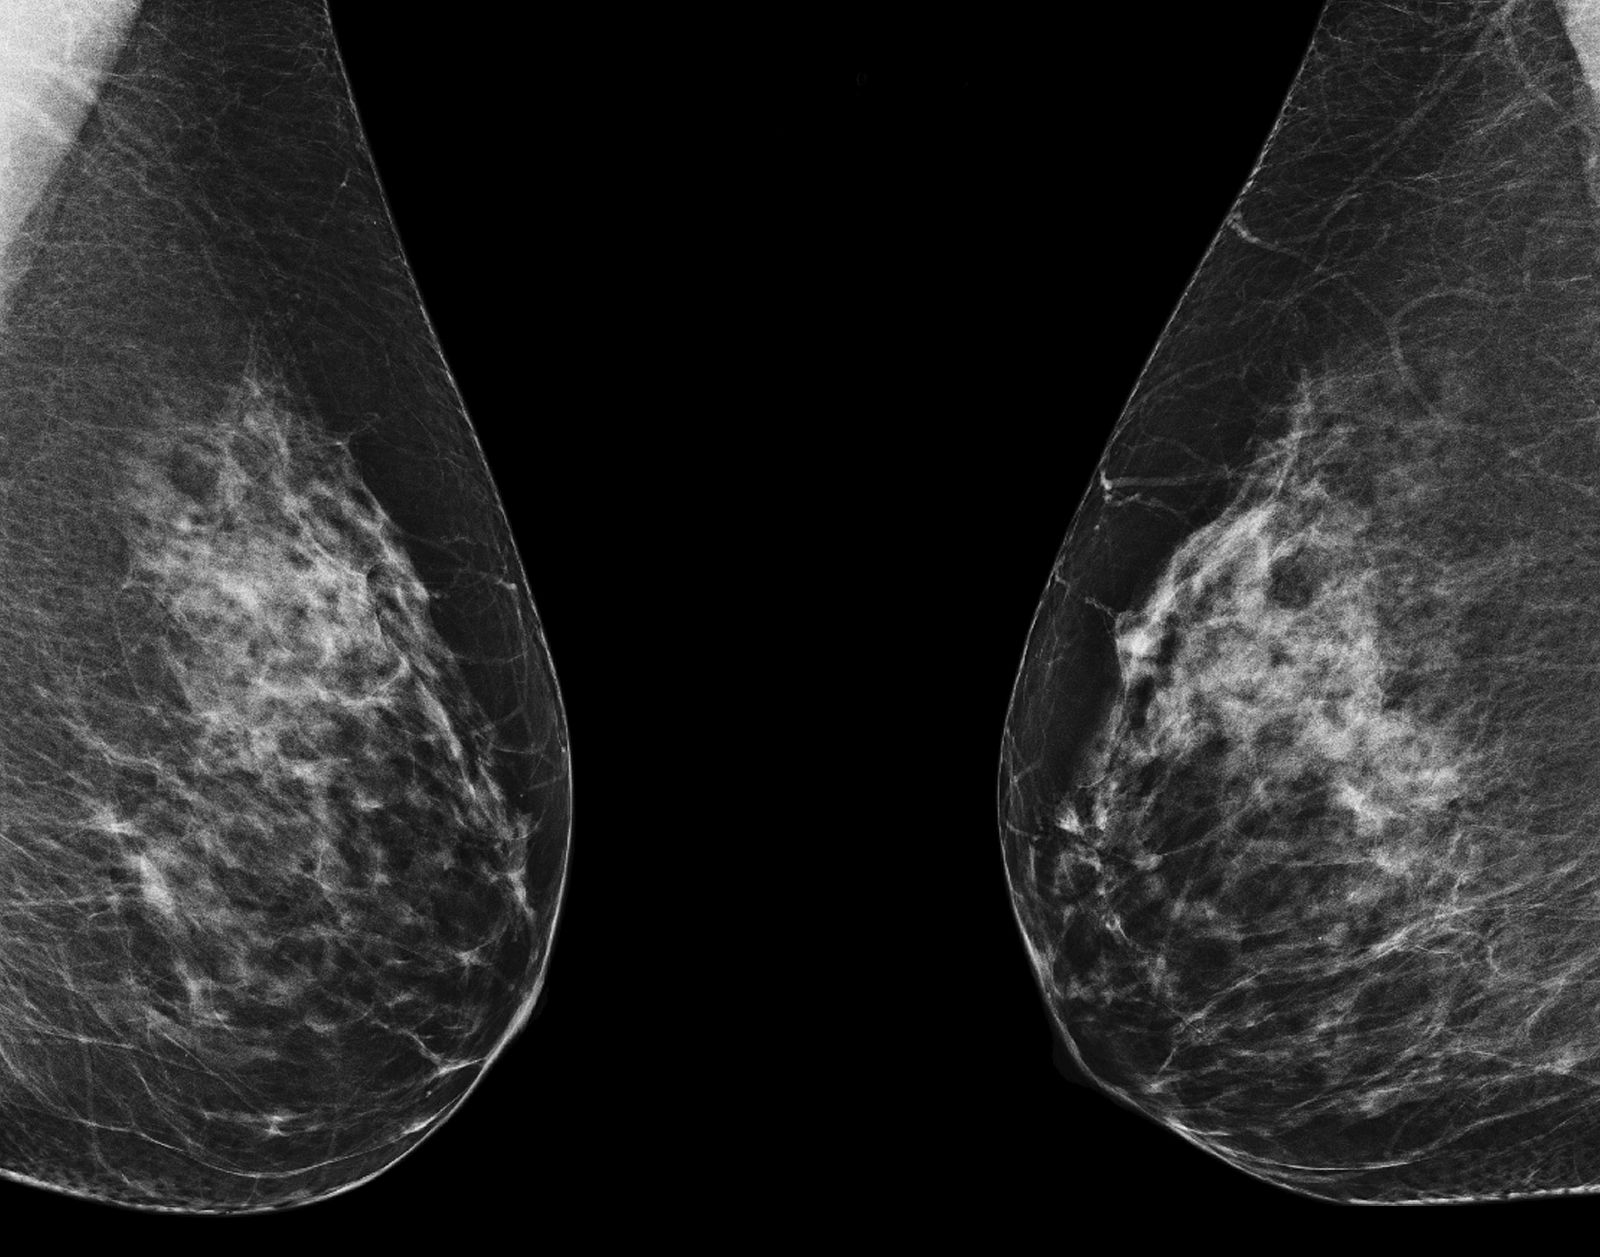

Mamografía.